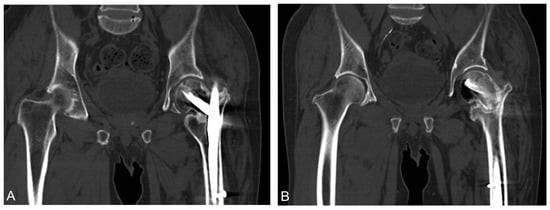

2. Case Report